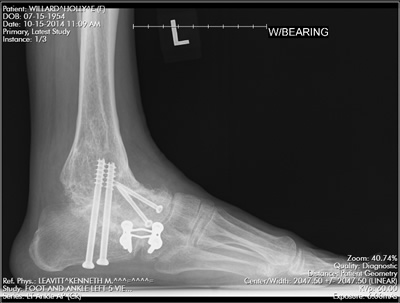

After doing the first fusion which failed badly and which I did because I was told "it should help so we should try it" I was not about to do another surgery unless someone could actually diagnose the source of my pain and none of the doctors from these "world renowned" Boston hospitals would even try to help me despite the fact that I could not walk and the pain was severe. Then, I found Dr. Leavitt. I called Dr. Leavitt's office and I got an appointment within one week. Dr. Leavitt started figuring out what was wrong at the very first visit. Dr. Leavitt did x-rays and a CT scan and gave me all the results during this first visit and then I knew I had finally found the best orthopedist in Boston. I had multiple appointments over the next 6 to 8 weeks as Dr. Leavitt systematically diagnosed exactly where all the pain was coming from. He precisely pinpointed which joints needed to be fused and he diagnosed the source of the original pain across the bottom of my foot as a condition called Tarsal Tunnel Syndrome which is similar to Carpal Tunnel Syndrome only it's in the bottom of my foot not in my wrist.

Dr. Leavitt performed the surgery in March, 2014 and I spent six months on crutches to allow proper healing. Dr. Leavitt also did a second surgery to specifically treat Tarsal Tunnel Syndrome which was the cause of my original pain but which had never been diagnosed by multiple other orthopedic surgeons prior to Dr. Leavitt. Once my foot and ankle was 100% healed from the fusion surgeries, I resumed my normal activities with no pain at all in my foot and ankle. It has been a long journey that started in 2009, but now, as of July 2017, I am able to do everything I want to do with very minimal pain. I am eternally grateful to have met this incredibly intelligent, talented, and compassionate doctor. Dr. Leavitt not only saved my foot, he also restored my life.